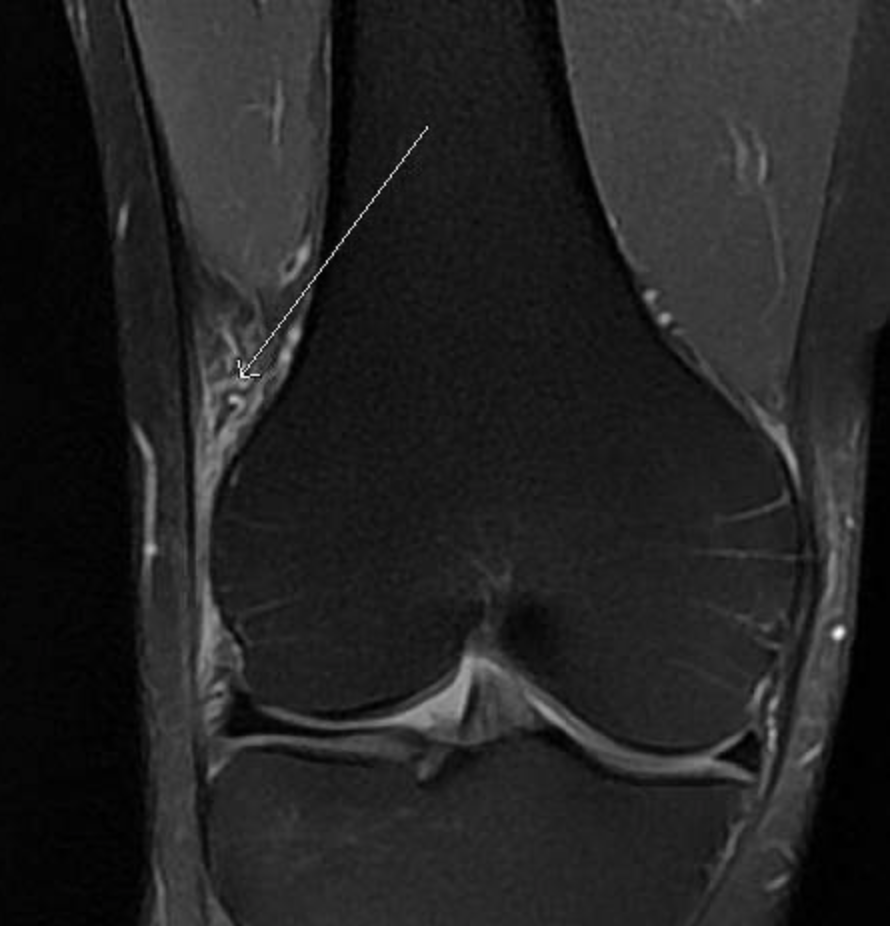

Irm avec inflammation de la bandelette ilio tibiale (flèche)- Dr Dumoulin